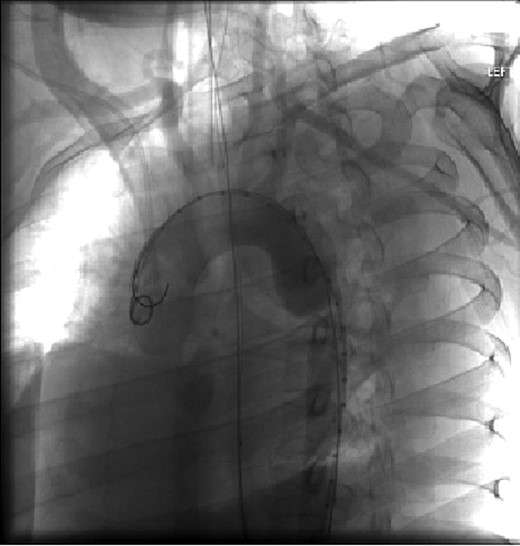

The patient was taken emergently to the vascular hybrid room where the left common femoral was accessed percutaneously. A 26–21 mm diameter tapered Gore Tag® endograft was positioned at the left subclavian artery and deployed. The pseudoaneurysm was sealed and the transection resolved (Figs 2 and 3).

Aortic arch and descending thoracic aorta visualized by CTA with contrast pre-placement of stent.